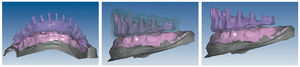

Mediante el uso de un escáner óptico de luz estructurada, los protocolos CAD registran los primeros datos relativos al modelo maestro con las correspondientes posiciones de implante (figs. 87 y 92). En el siguiente paso tiene lugar la digitalización de la planificación, previamente realizada en cera de escaneo matificada, de la restauración definitiva (figs. 88, 90 y 93). La subsiguiente conciliación de los datos mediante el uso del software de diseño dental permite al protésico planificar virtualmente el resto del procedimiento (figs. 89 y 91, 94 a 96) a partir del diseño de las estructuras (figs. 97 y 98).

Fig. 89. Planificación CAD de la estructura del maxilar superior.

Fig. 91. El diseño definitivo de la estructura para el maxilar superior.

Figs. 94 a 95. Planificación CAD de la estructura del maxilar inferior, en representación lingual y vestibular.

Figs. 96 a 98. El diseño definitivo de la estructura del maxilar inferior, desde distintas perspectivas.